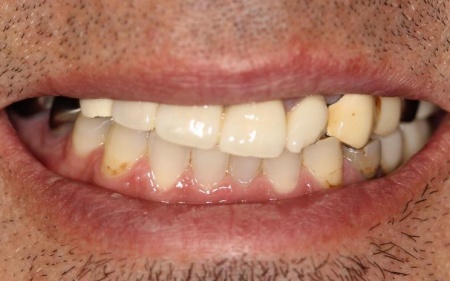

治療前

治療後